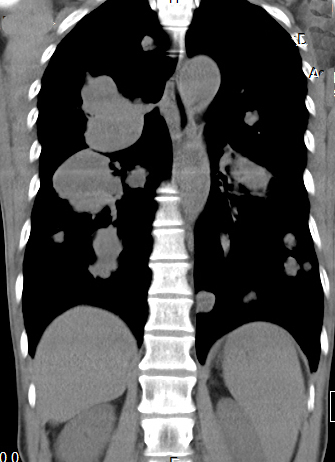

[影像描述]

双肺多发转移灶,大小不等,呈棉花团样

CT表现为粟粒、单发、多发大小不等结节,呈圆形或椭圆形,密度均匀、轮廓清楚,肺野为著。

1、肺内单发或多发球型结节影,大小不一,边缘光滑,密度均匀,多分布于肺外围

2、肺内软组织团块影!单发或多发,有分叶或毛刺,部分有空洞

3、两肺布满粟粒样结节

4、肺纹理呈网状改变或沿淋巴管呈细小结节状改变,HRCT表现为小叶间隔增厚,沿肺纹理有细小结节影,同一患者出现多种形态转移征象.